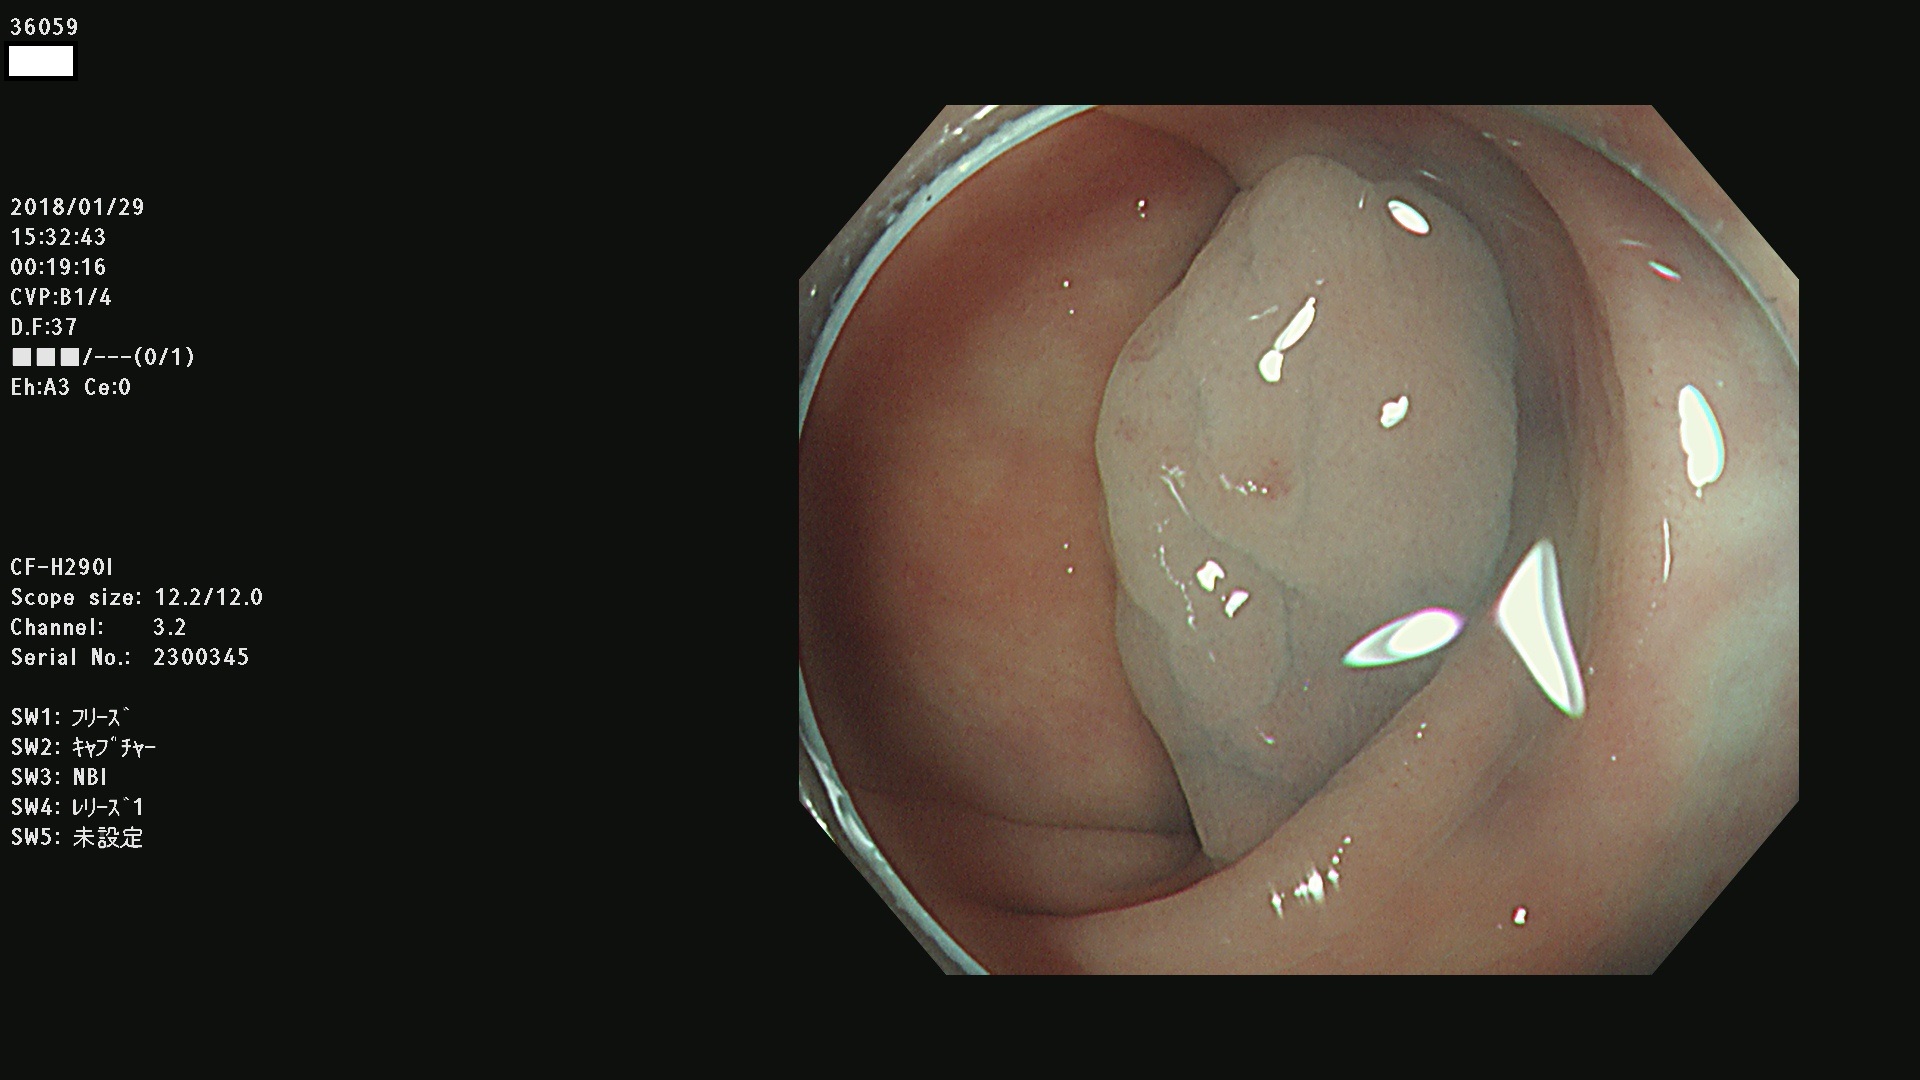

36000 36001 36003 36004 36008 36009 36012 36013(SSA/Pのみ) 36015 36016 36017 36021 36022 36023 36027 36030 36033(SSA/Pのみ) 36036 36037 36042 36044 36045 36046 36047 36051 36053 36054 36055 36056 36057 36058 36059 36060 36061 36062 36073(SSA/Pのみ) 36074 36075 36076 36078 36081 36082 36083 36089 36090(SSA/Pのみ) 36094 36096

発見困難で危険性の高い平坦型病変(上記100名より抽出)